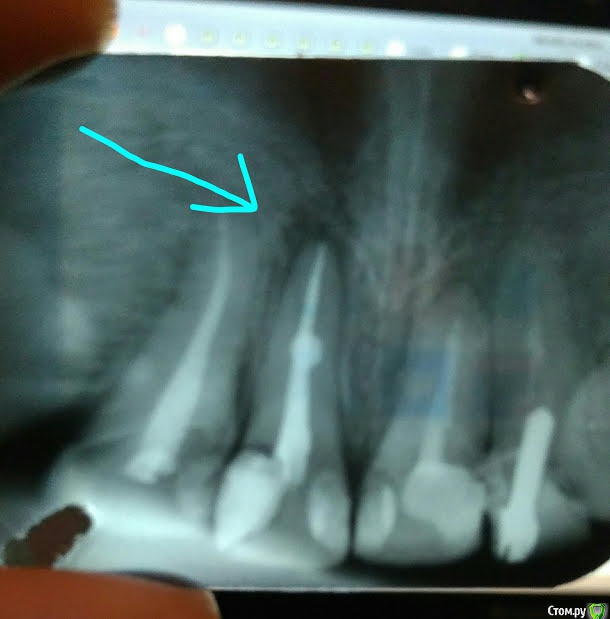

ya2mama Опубликовано 30 марта, 2018 Автор Поделиться Опубликовано 30 марта, 2018 Покажите rgПосле пломбирования светопломбой снимок не делался. А накануне, 4 днями ранее был получен вот такой (мой снимок из соседней темы): Ссылка на комментарий

dok1 Опубликовано 30 марта, 2018 Поделиться Опубликовано 30 марта, 2018 Все 4 резца имеет смысл покрыть коронками всилу большого объёма пломбировачного материала, восстанавливающего зубы с нескольких поверхностей. Идеальные в эстетическом плане реставрации пломбировочным материалом сделать можно. Это стоит, обычно, дороже простой пломбы. Но в вашем случае неоправданно. В искомом зубе канал запломбирован хорошо. При правильной обработке канала перед пломбированием разряжение уйдёт. 3 Ссылка на комментарий